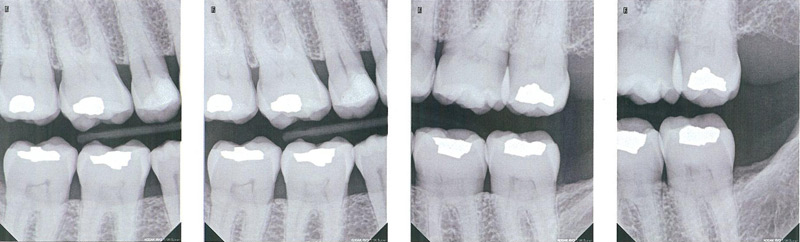

Panographs

A common screening film is the panograph, which gives an overview of both upper and lower arches and the surrounding anatomic structures. When taking this x-ray no film is placed in the patient's mouth, and the x-ray machine circles around the head. While a useful screening tool, and important for implant placement, it lacks the detail needed for a complete periodontal exam.